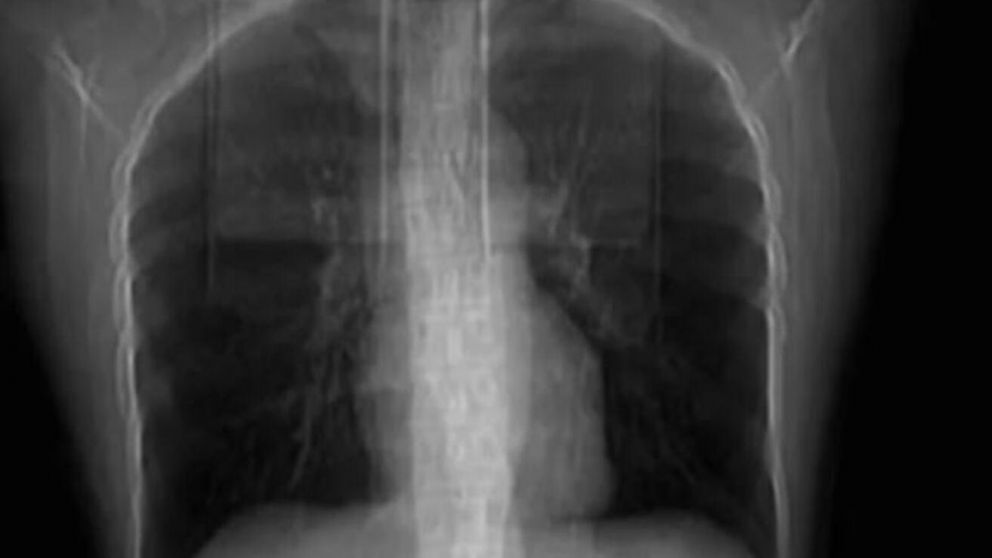

Pero cuando las horas pasaron y empezó a tener un dolor tremendo al hablar y dificultades para respirar, a Huang no le quedó otra que recurrir a un profesional. El médico que la atendió le hizo una tomografía que, llamativamente, le arrojó como resultado que tenía cuatro costillas rotas.